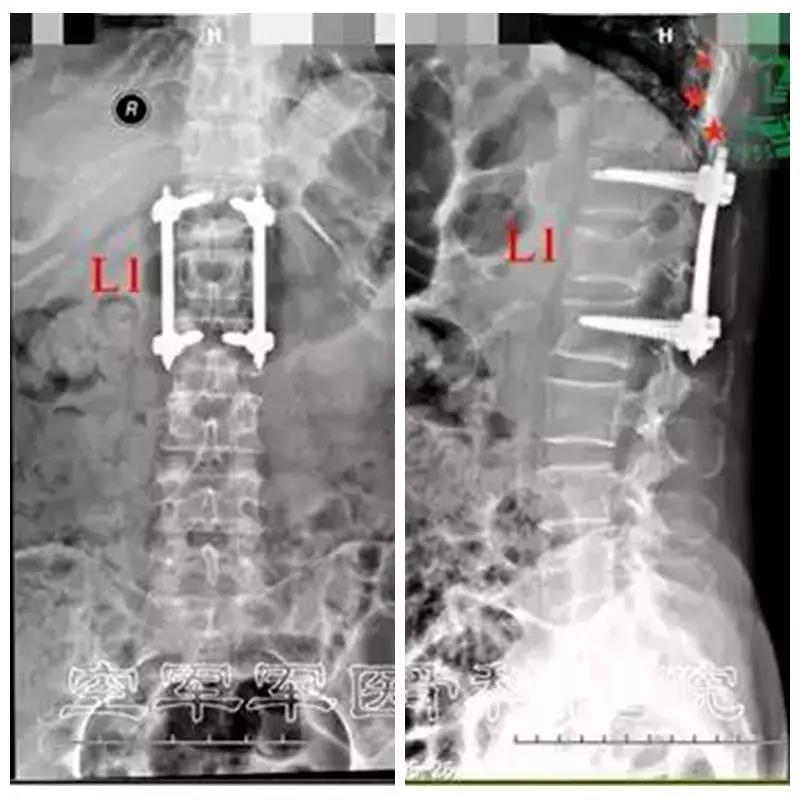

术后X线片正侧位及三维CT